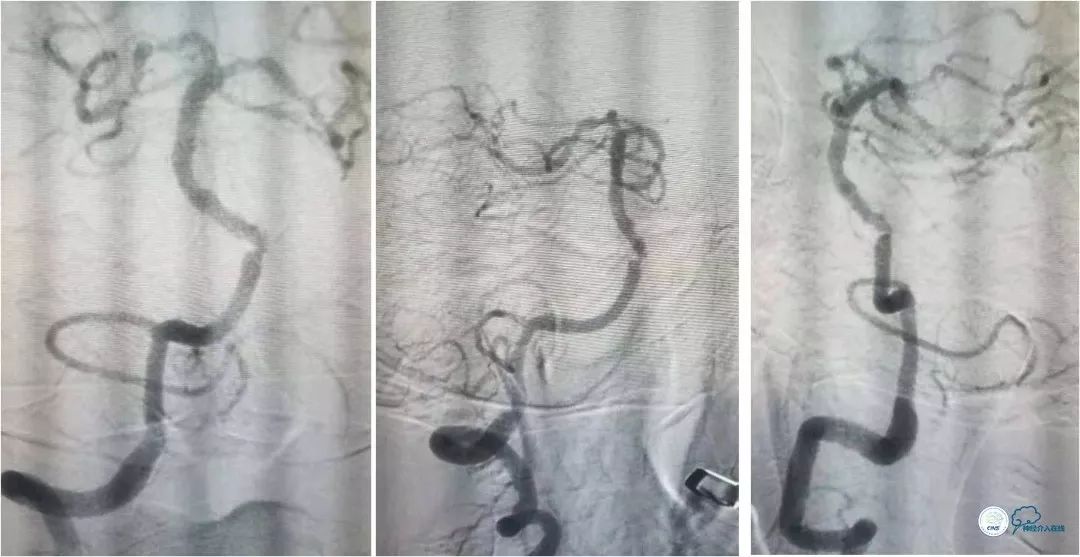

全麻下右侧股动脉穿刺置入6F动脉鞘, 6F导引导管至左椎动脉V2段远端,术前造影示左椎动脉V4段与基底动脉交界处重度狭窄(图8)。

图8

路径图下经交换技术送入Transend微导丝(0.014″,300cm)至左大脑后动脉。沿微导丝送入Gateway球囊(2.25mm×9mm)于狭窄处预扩张,扩张后造影提示狭窄程度明显改善(图9)。

图9

撤出球囊导管,送入wingspan (2.5mm x 15mm )自膨式支架,造影提示支架释放后支架贴壁良好,前向血流TICI 3级。右椎动脉V4段经返流显影,但病变受支架影响显示狭窄程度加重(图10)。

图10